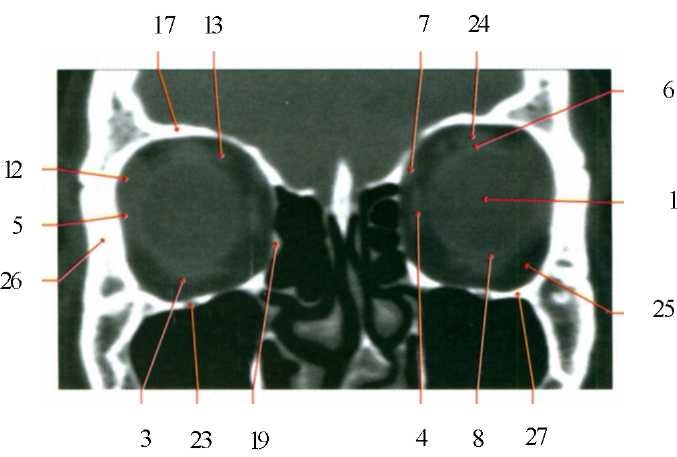

КТ-графики и изображение строения глаза